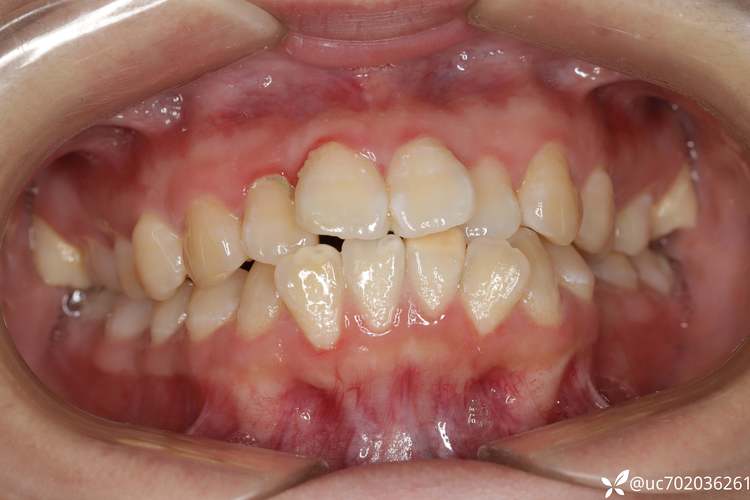

安氏三类错颌畸形,俗称“地包天”,是临床上较为复杂的错颌类型,主要表现为下颌前突、上颌后缩或两者并存,前牙呈反颌关系(下前牙咬在上前牙唇侧),磨牙关系为近中关系(下颌第一磨牙的近中颊尖咬合于上颌第一磨牙的近中沟),对于此类错颌,正畸治疗是核心手段,而拔牙矫治则是部分病例的关键策略,其目的是通过解除牙列拥挤、调整颌骨位置关系、改善面部美观及咬合功能。

安氏三类错颌的病因复杂,包括遗传因素(如下颌骨发育过度、上颌骨发育不足)、环境因素(如儿童期不良习惯,如咬上唇、口呼吸、长期吮指等)、替牙障碍(如下颌乳牙早致下颌前移、上颌乳牙滞留导致上颌前牙萌出不足)及局部因素(如上颌前牙缺失、下颌前牙多生牙等),根据病因和骨骼表现,可分为牙性III类(仅牙齿位置异常,无明显骨骼问题)、骨性III类(上下颌骨发育不协调,常伴面部畸形)和功能性III类(由咬合干扰或下颌前伸习惯导致,下颌可后退至中性关系)。

骨性III类倾向的牙性代偿